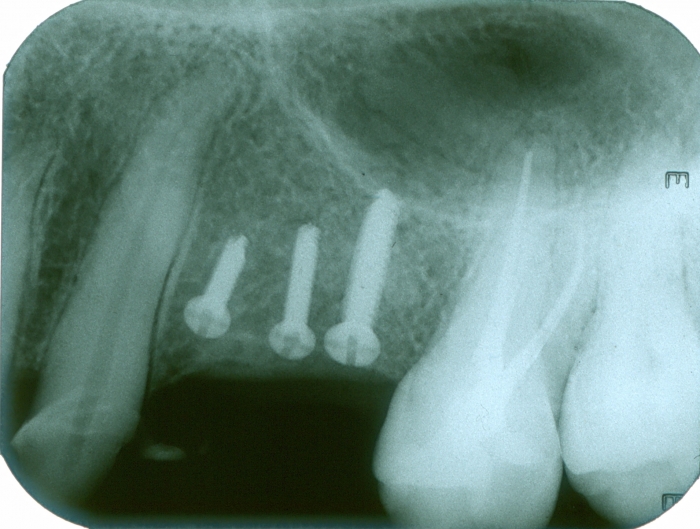

Raio X dos implantes instalados